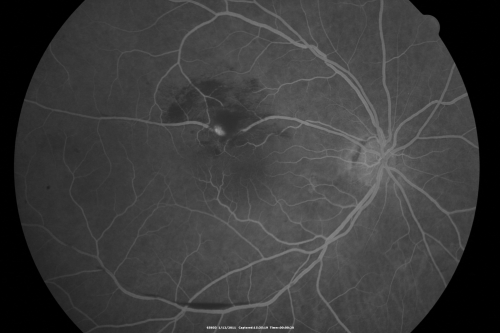

Retinal Arterial Macroaneurysm - Increased Swelling after Laser

65-year-old woman was seen in the office on January 12, 2011.   She has noticed decreased vision in the right eye for the last two or three weeks.  She has had some discomfort in both eyes as well.  She has a history of low blood pressure, but she does have high cholesterol.

VISUAL ACUITY:  OD 20/60